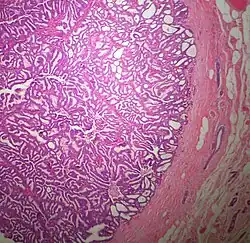

The microscopic histopathology of typical PDCIS lesions (refer to adjacent high-power photomicrograph) prepared with a hematoxylin and eosin stain consists of mammary ducts that have papillary fronds (i.e. thin, finger-like or leaf-like structures) lined with one or several layers of neoplastic, columnar-shaped epithelial cells (i.e. tall, narrow cells with their nuclei close to the site of their ductal attachment).[4] The fronds have branching fibrovascular cores. Epithelial cells lining the fronds' inner surfaces commonly form solid, cribriform (i.e. large nests of cells perforated by many rounded, variably sized spaces), or micro-papillary patterns. There may be a second population of epithelial cells lining the papillae that have abundant clear cytoplasm in addition to the usual neoplastic epithelial cells which line the papillae. These cells, which are not myoepithelial cells, have been termed globoid cells.[7] They have eosinophilic cytoplasm (i.e. pink or red cytoplasm due to its uptake of eosin stain).[6] PDCIS tumors with these cells have been termed dimorphic variants of PDCIS.[3] Myoepithelial cells are typically present at the periphery of the fronds but absent within the involved ducts.[4][7] The presence of a fibrous capsule and/or absence of peripherally located myoepithelial cells are strong indicators that the tumor is an ESP rather than a PDCIS.[3] PDCIS tissues may also contain areas of "Comedo-type necrosis", i.e. areas where dead cells have accumulated.[6]

The microscopic histopathology (refer to adjacent high-power photomicrograph) of EPC tissues typically shows papillary structures with fibrovascular cores and proliferating neoplastic epithelial cells growing within cystic spaces, all of which are enclosed within a dense fibrous capsule. In general, EPC tumors do not have areas of neuroendocrine degeneration or myoepithelial cells.[6] The presence of a dense fibrous capsule distinguishes EPC from other papillary breast tumors, particularly PDCIS;[3] the absence of neuroendocrine differentiation areas helps distinguishes EPC from SPC tumors;[3] and the absence of peripherally located myoepithelial cells helps distinguish EPC from PDCIS tumors.[7] EPC tumors may be totally contained within their fibrous capsules or have one or more areas that have invaded through the capsule to normal breast tissues and/or chest muscles; these two variants are termed in situ EPC and infiltrative EPC, respectively.[3][5] In a study of 25 individuals with EPC, 14 had in situ and 11 had invasive disease with 6 of the invasive tumors rated as high grade (see high grade tumors) based on their microscopic histopathology.[5] Rarely, EPC tumors metastasize to nearby sentinel lymph nodes, other nearby axillary lymph nodes, and/or distant tissues; these metastases have in general shown papillary morphologic features similar to their primary tumors.[6] Uncommonly, EPC tumors co-exists with nearby PDCIS,[7] invasive carcinoma of no special type, invasive cribriform carcinoma of the breast, mucinous carcinoma, or tubular carcinoma[3] tumors.